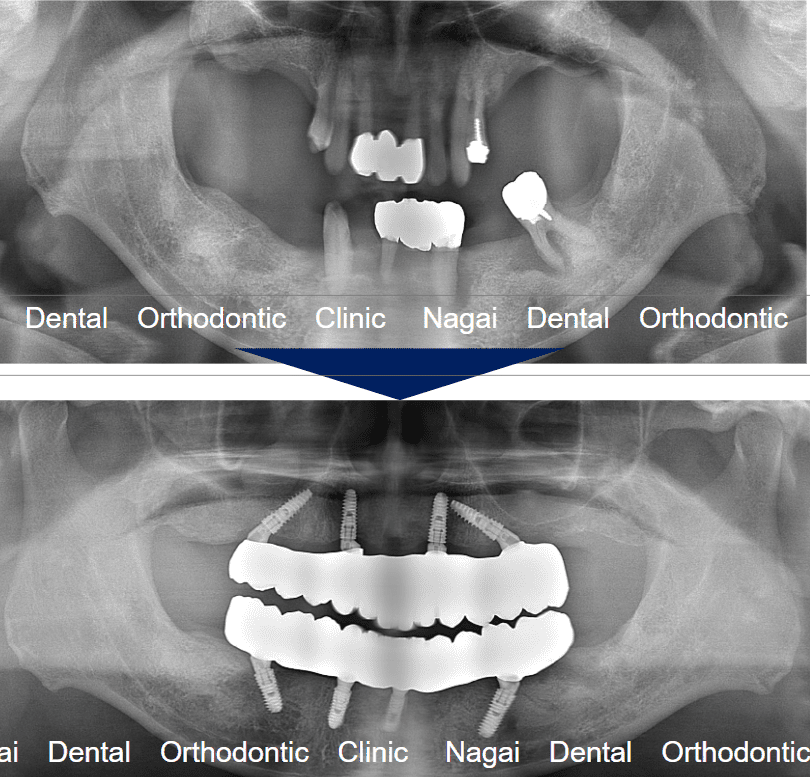

【口腔内の詳細変化】

▲部分欠損や咬合の乱れに伴う咀嚼能率低下の改善を図りました

▲部分欠損や咬合の乱れに伴う咀嚼能率低下の改善を図りました

▲インプラントによる固定式補綴物で、全体的な咬合の再構築を目指しました

| 年齢/性別 | 50代/男性 |

| 背景 | 左側での咀嚼困難や、年々広がる歯間の隙間、および咀嚼時の不具合を主訴に来院されました。過去に部分入れ歯の適応を受けたものの、装着時の痛みから使用を中断されており、取り外し式の入れ歯以外の治療法を希望されていました。事前の咀嚼能率検査でも数値の低下が認められ、速やかな機能回復が求められる状態でした。 |

| 治療期間 | 約7か月(通院12回) |

| 費用 | 6,600,000円(税込)(片顎 3,300,000円×2) |